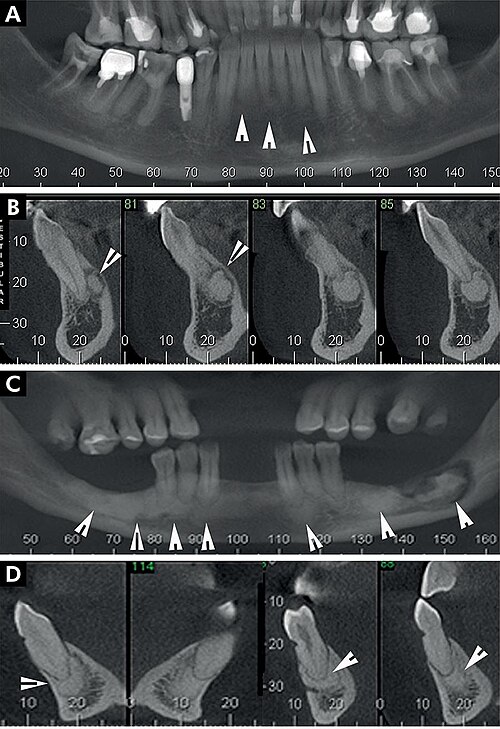

Orthopantomogram (OPG) phantom showing full mandible and maxilla with all teeth, TMJ, sinuses, and surrounding anatomy

Cone-beam CT phantom of the maxillofacial region showing teeth, alveolar bone, sinuses, nasal cavity, and mandibular...

Dental phantom showing common pathology: carious lesions, periapical abscess, root resorption, and a metallic restoration